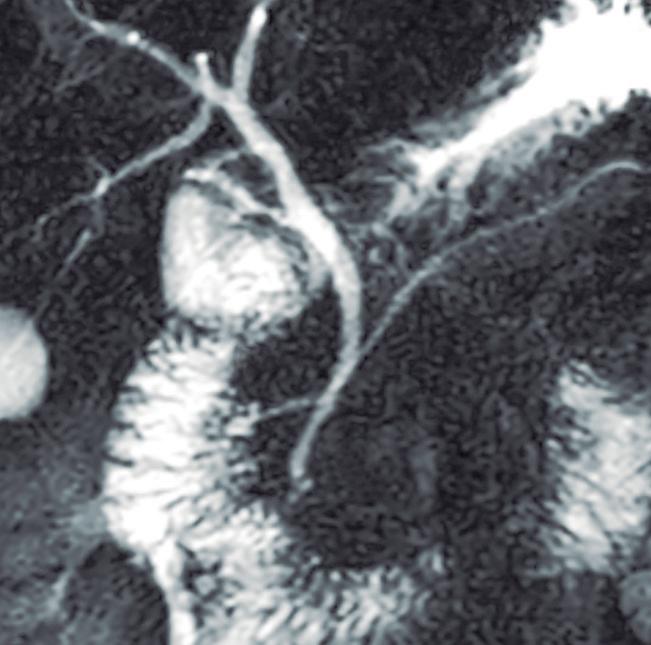

Consiste en una anomalía de la migración del brote pancreático ventral, el cual no rota o lo hace de manera incompleta, resultando en la presencia de tejido glandular pancreático a la derecha del duodeno, rodeando a su 2° porción (Figura 8). Han sido descriptos dos subtipos: el extramural, donde el conducto de Wirsung rodea al duodeno uniéndose al conducto pancreático principal; y el intramural, donde el tejido pancreático se entremezcla con la pared duodenal y sus secreciones drenan directamente a la luz a través de conductos muy pequeños.16

En las imágenes encontramos parénquima pancreático rodeando a la 2° porción duodenal, habitualmente en toda su circunferencia y en ocasiones de manera incompleta. En la colangio-RM es posible visualizar al conducto pancreático a la derecha del duodeno, con un recorrido que se dirige a la ubicación de la papila mayor (Figura 9).17

A) Resonancia magnética secuencia T1 con gadolinio, plano axial. Las flechas señalan el parénquima del páncreas prolongado hacia la derecha “abrazando” a la 2° porción duodenal (cabeza de flecha). B) Resonancia magnética, secuencia T1 con gadolinio, plano axial, corte más caudal al previo. Las flechas nos muestran al páncreas rodeando de manera completa a la 2° porción del duodeno. C) Resonancia magnética, secuencia T2, plano coronal. La flecha señala presencia de parénquima glandular y conducto pancreático a la derecha del duodeno (cabezas de flecha). D) Resonancia magnética, secuencia T2, plano coronal, corte posterior al previo. El páncreas anular y su conducto de drenaje rodean en forma completa al duodeno (cabezas de flecha). E) Colangio-RM. El conducto del páncreas ventral (flechas) hace un giro, rodea al duodeno (cabeza de flecha) y se une al conducto pancreático principal para drenar en la papila mayor. F) Colangio-RM. La imagen magnificada muestra con mayor detalle el recorrido del conducto de Wirsung en el contexto de un páncreas anular.